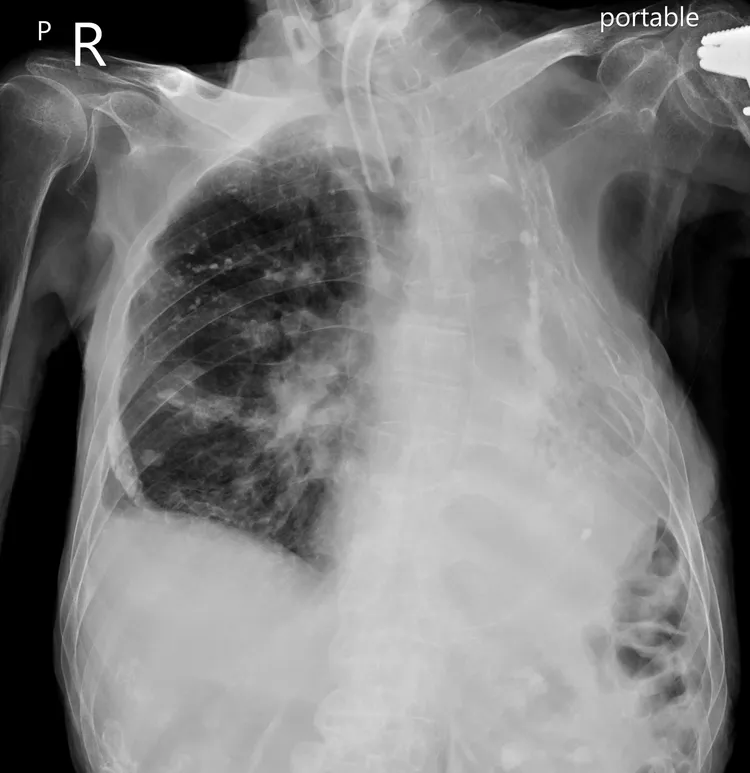

蘇一峰在臉書分享一張X光照片,表示「我病人99歲人瑞爺爺的X光,大家看看他的肋骨發生了什麼事?」隨後並再次發文分享病患過去的治療方式,「你敢相信嗎?外科醫師把病人的肋骨一根一根切下來,足足切了六七根,是為了救他的命」。

因此病患在醫生的建議下,動了胸腔整形手術,拿掉了6、7根肋骨,而動了手術後病情漸漸穩定下來,「沒想到還能活到高齡99歲,在醫院遇到胸腔科蘇醫師」,蘇一峰感嘆對方現在失智臥床了,無法說清楚這段歷史,只剩下他身上的治療痕跡。

蘇一峰分享99歲病患的X光照。翻攝蘇一峰臉書